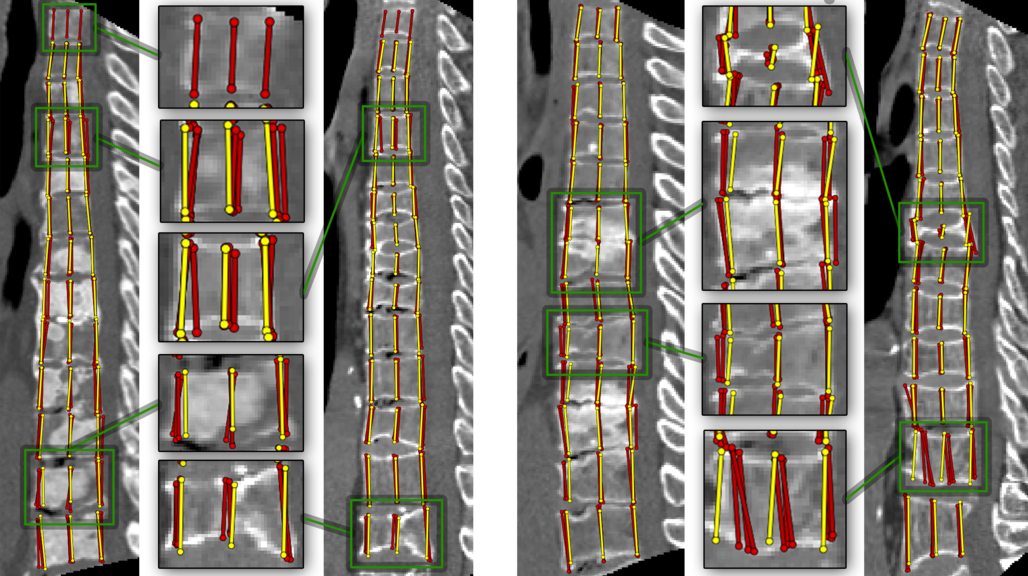

Figure 5: Two hard examples from the dataset. Colors denote the fractures severity.

Figure 6: Examples on which our model (yellow) performs poorly. Note the variability of the expert annotation (red).